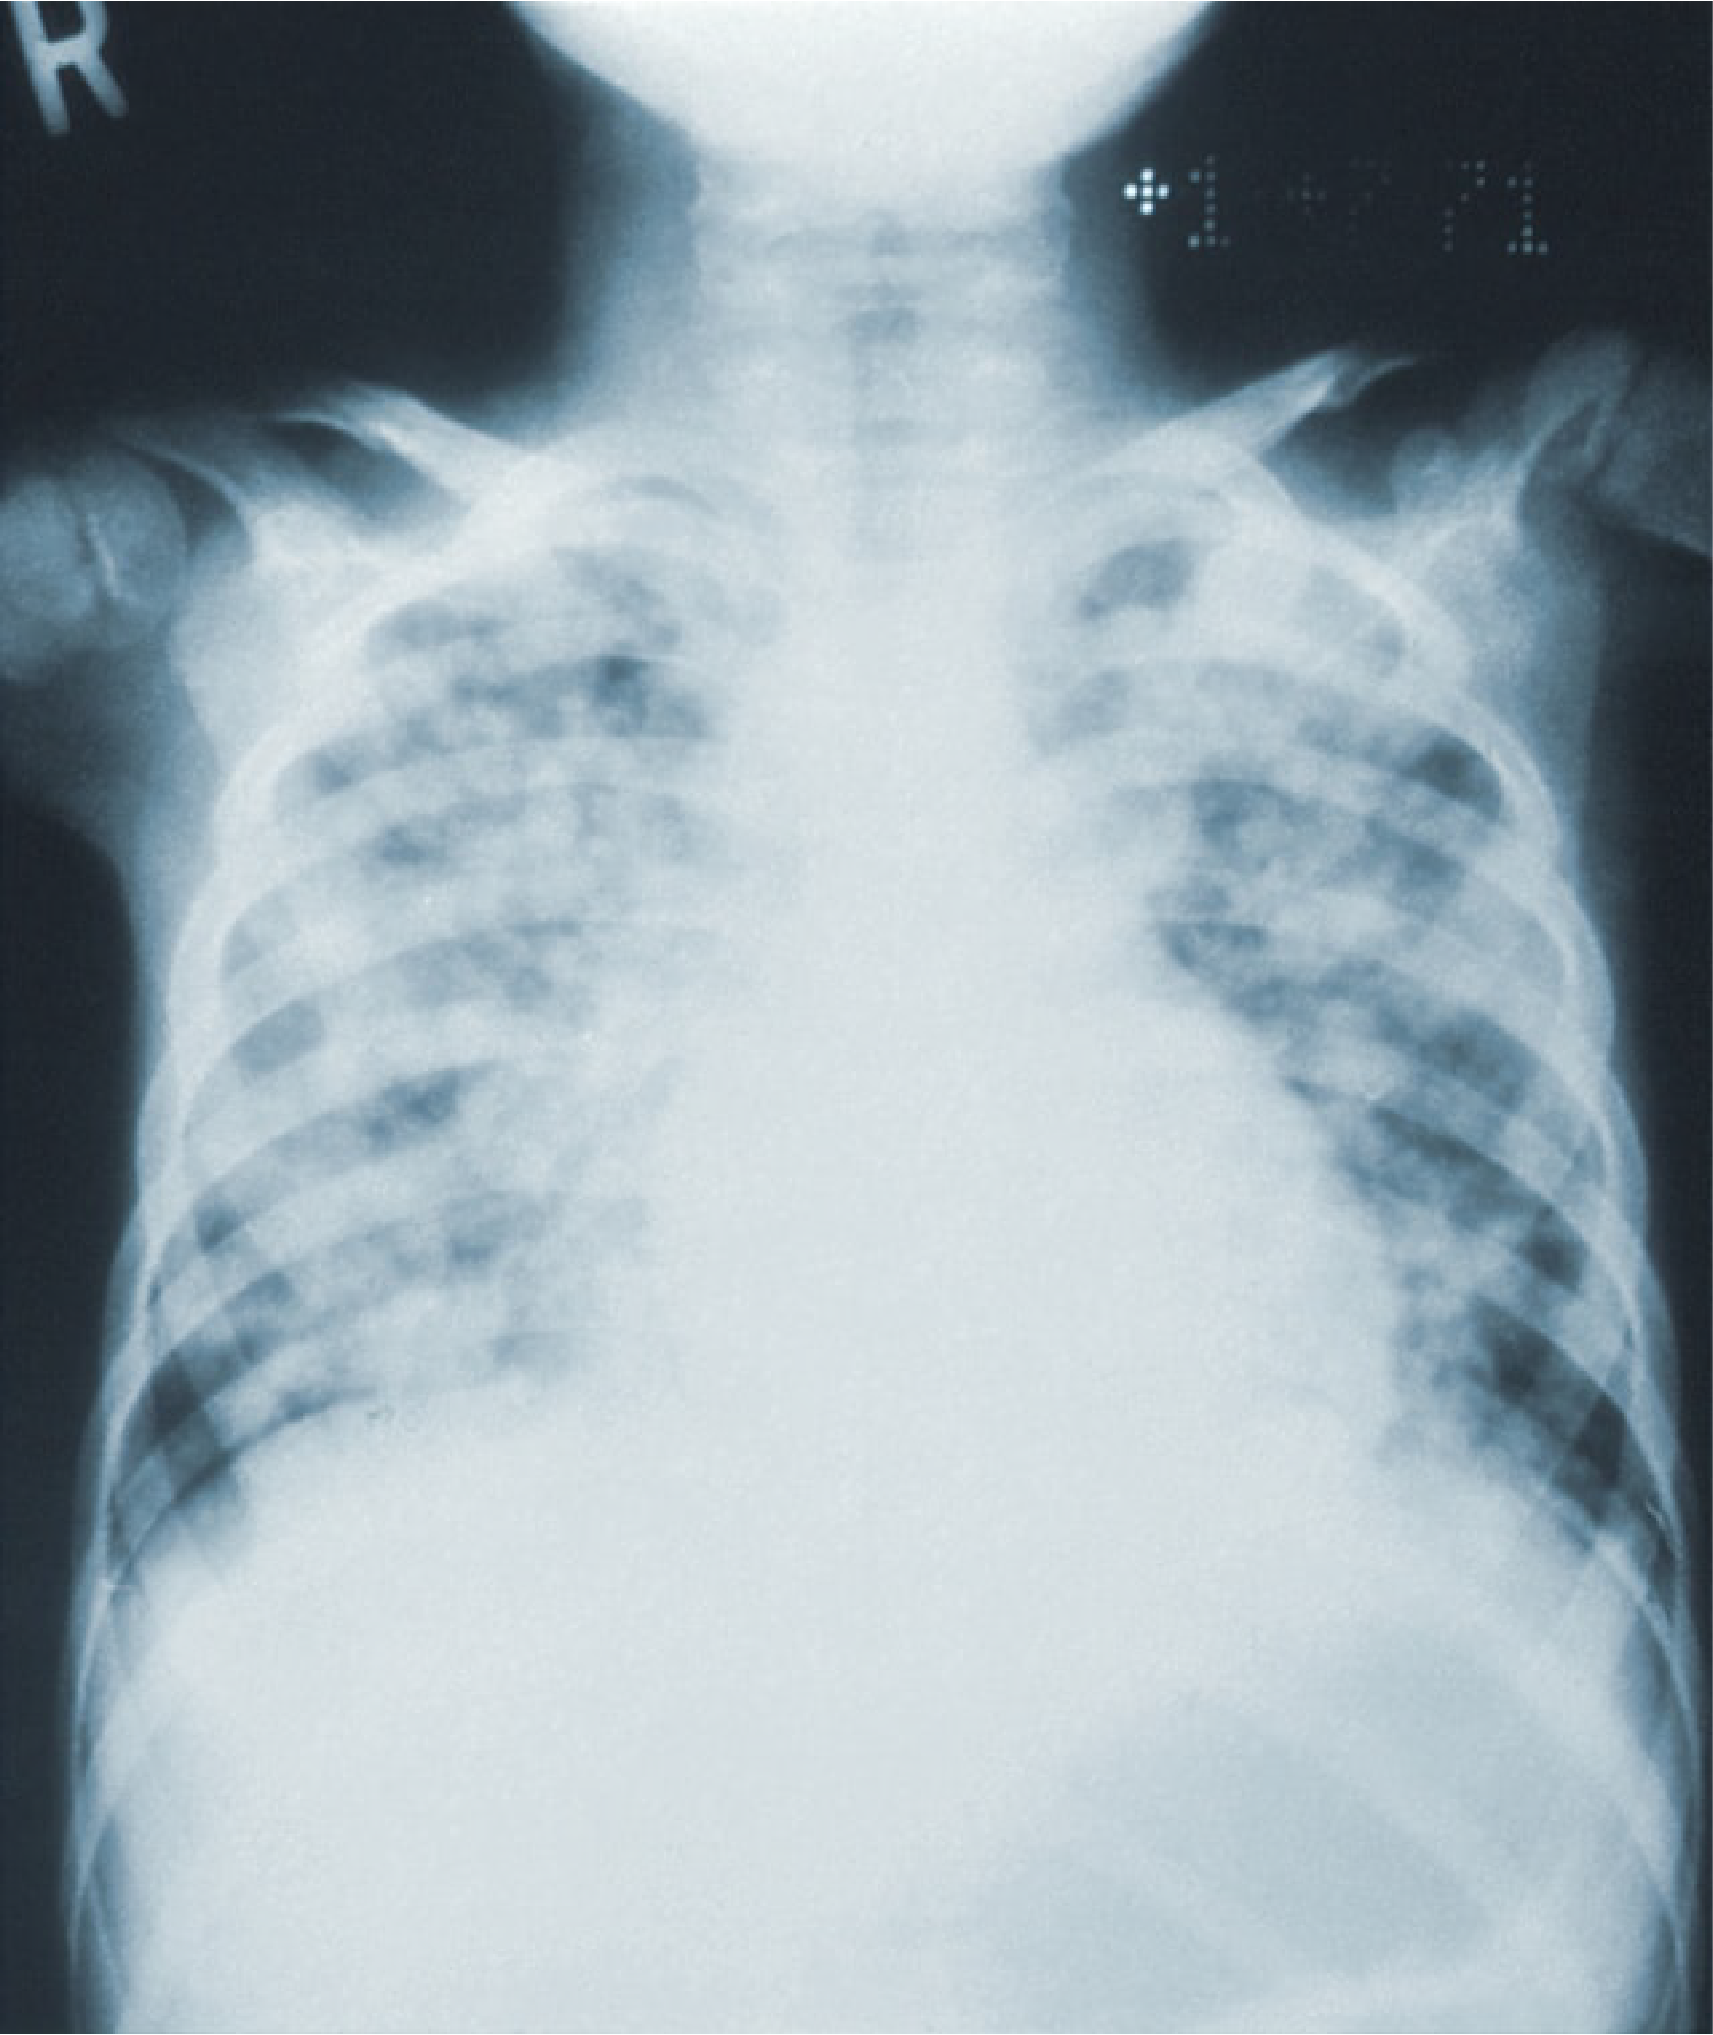

Cáncer de pulmón

El cáncer de pulmón es una enfermedad causada por el crecimiento anormal y desordenado de células en el tracto respiratorio y en el tejido pulmonar, lo que da lugar a la formación de un tumor.